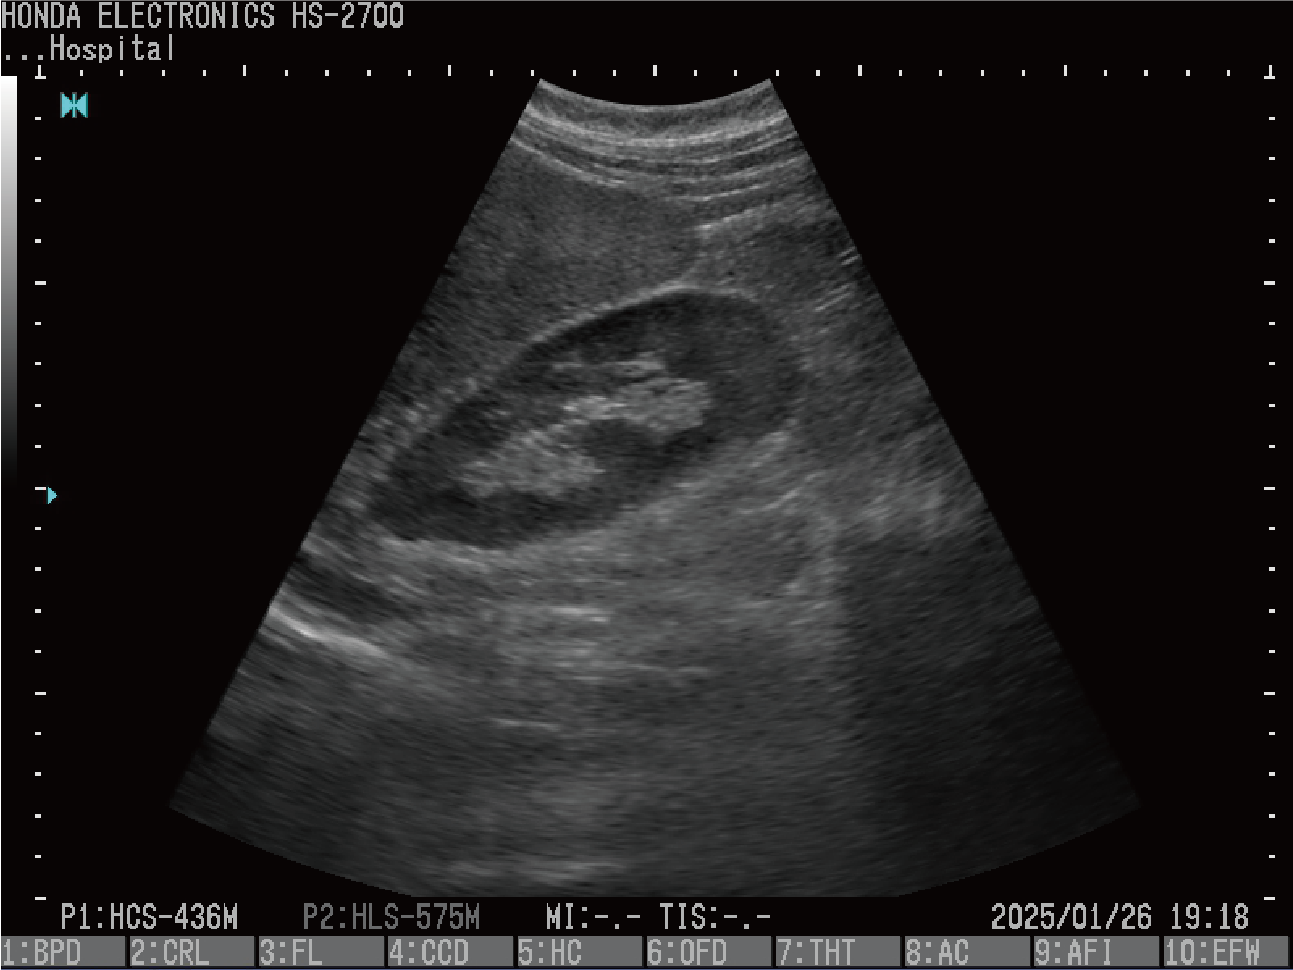

腎臓